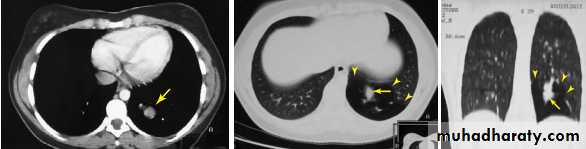

CT scan (Computed tomography scan )

Computed tomography or CT is an imaging modality that produces cross-sectional images representing the X-ray attenuation properties of

the body.

B- Spiral CT (Helical CT)

A technique that is widely used nowadays is helical CT.

The X-ray tube rotates continuously around the

patient, just as in 2D CT. At the same time, the patient

is slowly translated through the gantry.

Multidetector spiral CT scan ( 16 slice , 32 slice , 64 ,128 and 256 slice) .

In modern CT scanners, the detector array consists of multiple detector rows, in order to measure several slices per rotation of the X-ray tube.